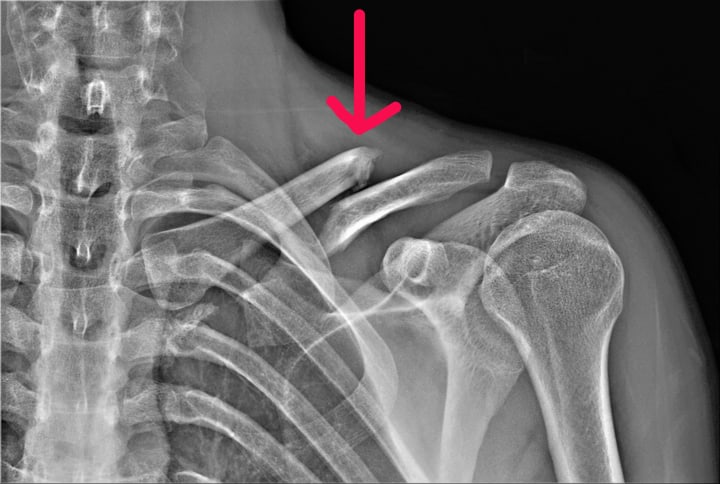

•Trauma or injury - Acute injuries like clavicle fractures, first rib fractures or whiplash injuries usually occur in the earlier decades of life and may lead to post-traumatic compressions, especially if healing does not proceed properly. The trauma itself or subsequent inflammation can narrow passages, entrap nerves or limit muscle function resulting in pain and disability.